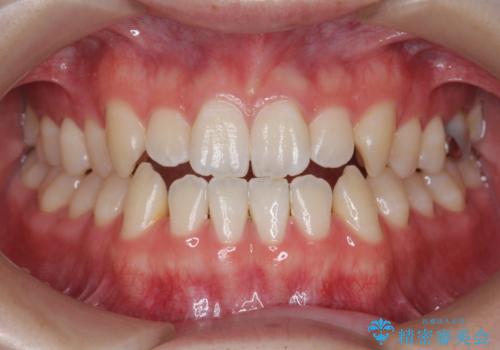

[ 前歯開咬 ] 前歯が噛んでいない マウスピース矯正治療

担当医 大元洋佑

![[ 前歯開咬 ] 前歯が噛んでいない マウスピース矯正治療の症例 治療後](https://seimitsushinbi.jp/wp/wp-content/uploads/2022/11/IMG_2488-500x350.jpg?v=1668218373)